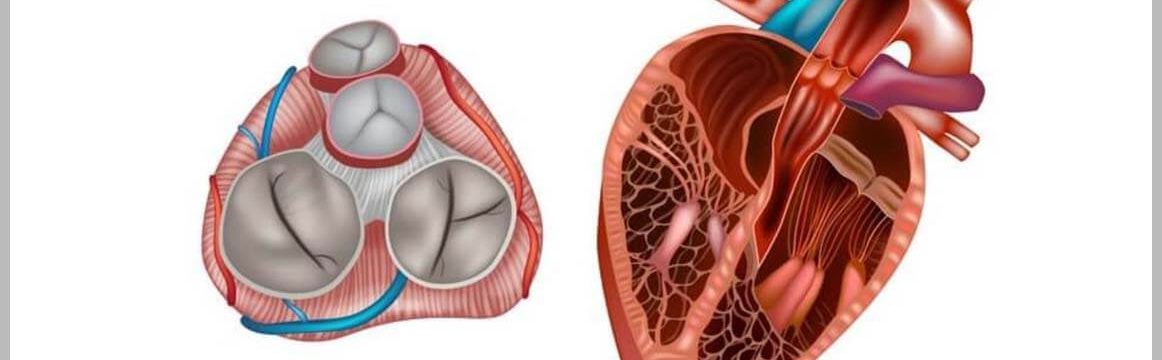

Kalp Kapak Hastalıkları Nedir?Kalp kapakçıkları, kanın doğru yönlere akmasını sağlayan organlardır. Bu kapakların düzgün çalışmaması, kanın geri kaçmasına veya yetersiz akışa n

Neden Kalp Kapakçığı Değişimi Gereklidir?Kalp kapakçıkları, kalbin kan pompalama işlevini yerine getirmesinde önemli bir rol oynar. Kapakçıklar hasar gördüğünde, kanın geri kaç